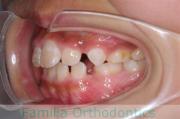

上顎

下顎

前歯の関係など

右側

正面

左側